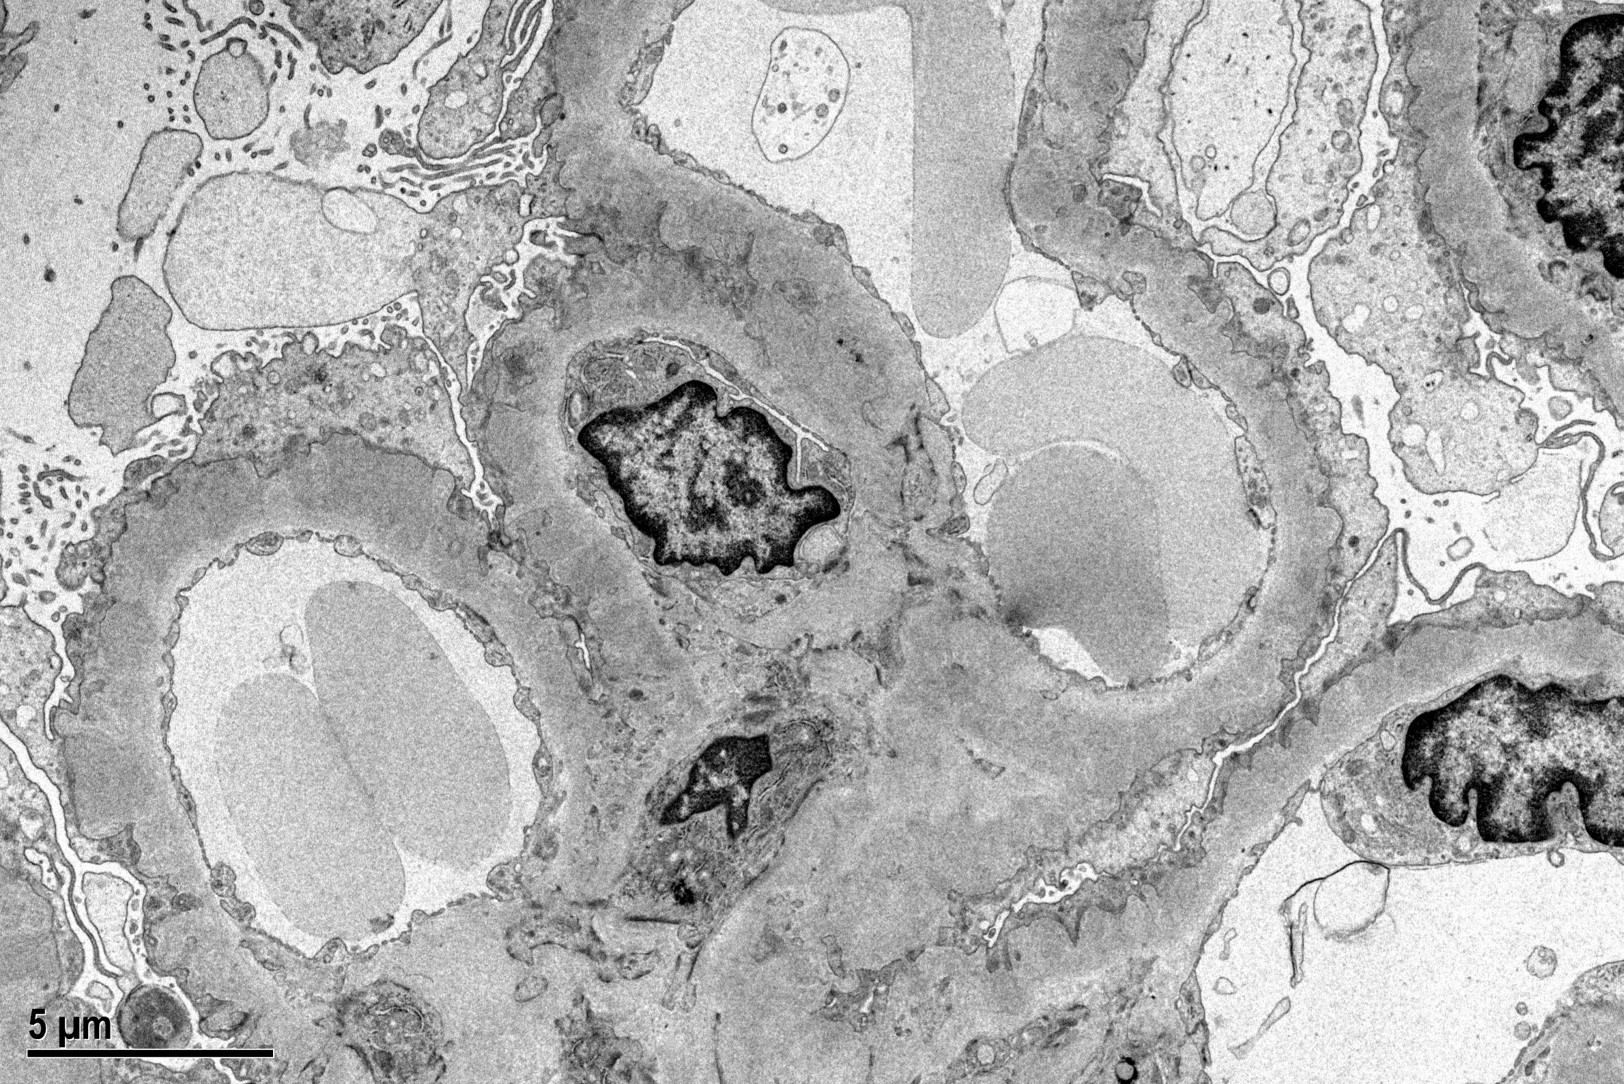

Immunofluorescence microscopy reveals a diffuse granular pattern of immunoglobulin G (IgG) staining along the GBM. The hallmark lesions on electron microscopy are subepithelial electron-dense deposits on the outer aspect of the GBM, effacement of the foot processes of the overlying podocytes, and expansion of the GBM by deposition of new extracellular matrix between the deposits (which are the "spikes" seen with the silver stain). Mesangial and/or subendothelial deposits of immunoglobulin are not seen in primary MN.